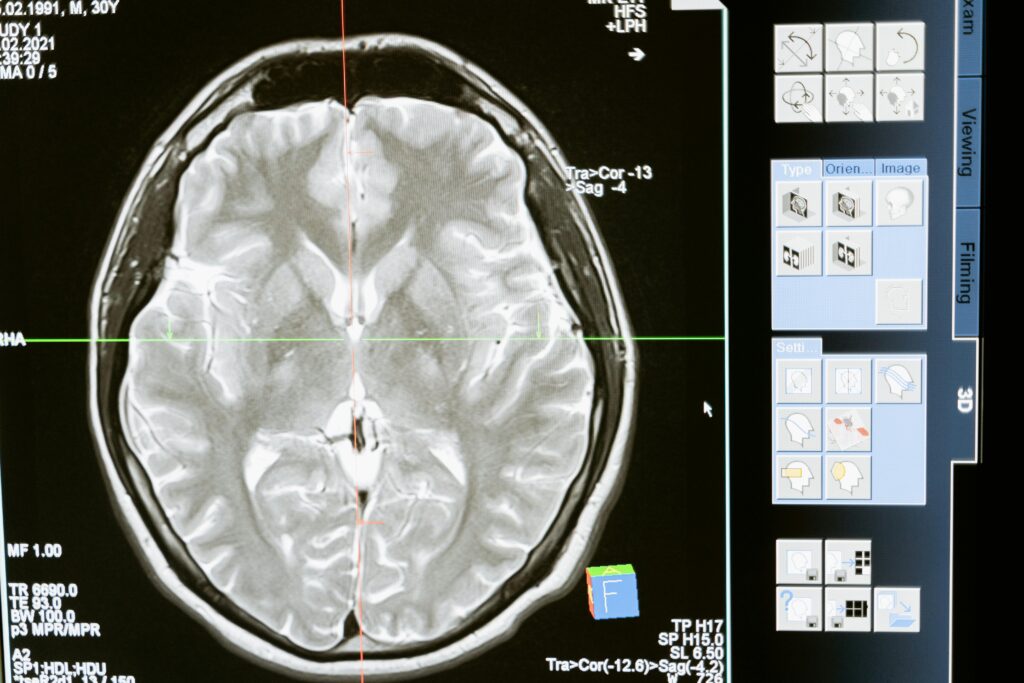

Diagnóstico y Tecnologías Modernas

Detectar Lesiones Cerebrales Traumáticas (LCT) puede ser complicado, especialmente cuando los síntomas no son evidentes. Las tecnologías avanzadas, como las Imágenes de Tensor de Difusión (ITD), han mejorado significativamente la capacidad de los médicos para evaluar el daño cerebral.

Las ITD permiten estudiar la materia blanca del cerebro, revelando alteraciones que no se detectan en resonancias convencionales. Estas imágenes muestran cómo el agua se mueve a través de los axones, permitiendo identificar lesiones axonales difusas y cuantificar la gravedad del daño. Esto ayuda a los médicos a planificar tratamientos más precisos y efectivos, adaptados a las necesidades de cada paciente.

Avances como la deconvolución esférica restringida (CSR) permiten mejorar la visualización de fibras complejas en el cerebro, aumentando la precisión del diagnóstico y la comprensión del impacto de la lesión. Gracias a estas técnicas, incluso lesiones que antes pasaban desapercibidas pueden ser detectadas y tratadas adecuadamente.